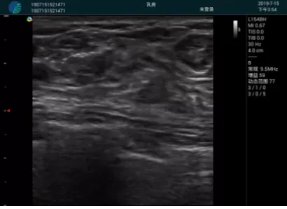

頸動脈血流充盈飽滿,無外溢